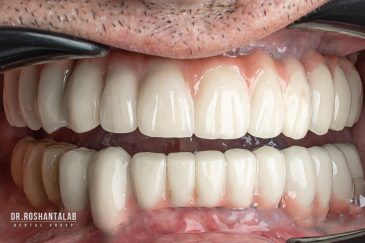

دندانپزشکی زیبایی

طراحی لبخند هالیوودی با متدهای لمینت سرامیکی دندان و کامپوزیت ونیر در کنار اصلاح فرم، خدمات بلیچینگ و روکش دندان، زیبایی چهره شما را تکمیل میکند.ترمیم دندان

برای اصلاح طرح لبخند بدون جلب توجه، از جدیدترین تکنولوژی الاینر و ارتودنسی شفاف استفاده کنید. ما تخصصیترین خدمات ارتودنسی دندان را با قیمت مناسب و شرایط اقساط ویژه ارائه میدهیم.کاشت دندان توسط بهترین متخصص ایمپلنت

انتخاب بهترین متخصص ایمپلنت که به تکنیکهای روز دنیا مسلط باشد، تضمینکننده سلامت فک و زیبایی لبخند شماست. در کلینیک دندانپزشکی دکتر روشنطلب، ما با بهرهگیری از تجهیزات دیجیتال در ۵ شعبه فعال (تهران، اصفهان، رشت و استانبول ترکیه)، خدمات تخصصی کاشت ایمپلنت دندان را برای بیمارانی که کیفیت و دقت برایشان اولویت دارد، ارائه میدهیم. در این متد، پروسه درمان با ظرافت بالا انجام شده؛ راهکاری ایدهآل برای کسانی که به دنبال درمان بدون درد با بالاترین نرخ موفقیت هستند.